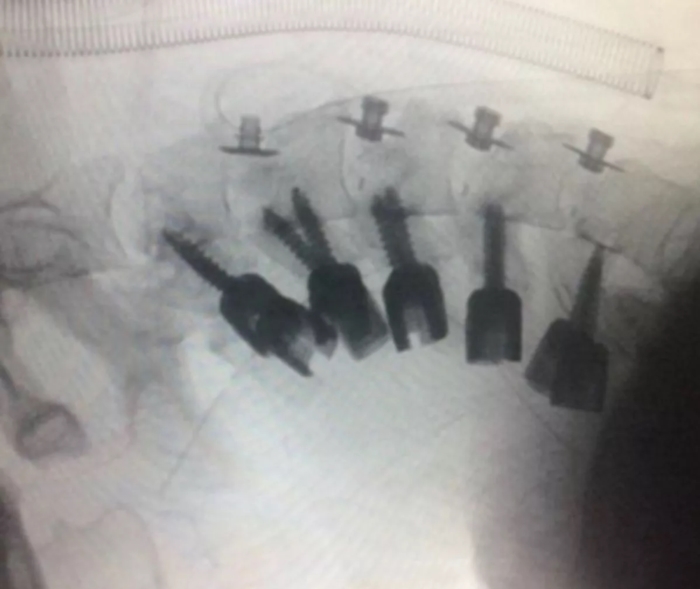

ภาพจาก Al-Zahra University Hospital

ได้เผยแพร่ภาพของผู้ป่วยชายรายหนึ่งวัย 23 ปี ซึ่งเกิดอาการป่วยแปลก

ลำคอมีสภาพโค้งงอจนพับไปข้างหนึ่ง

ภายหลังจากการตรวจเช็กร่างกายโดยละเอียด พบว่า ผู้ป่วยไม่มีอาการผิดปกติทางระบบประสาท แต่ผลการทำซีทีสแกนแสดงให้เห็นว่า กระดูกสันหลังของผู้ป่วยรายนี้ผิดรูปอย่างรุนแรง จำเป็นต้องทำการผ่าตัดเพื่อรักษาอาการ โดยแพทย์ต้องเอากระดูกที่ผิดรูปออกและใช้เทคนิคการผ่าตัดพิเศษเพื่อพยุงศีรษะขึ้น จนในที่สุดการผ่าตัดก็ประสบความสำเร็จ